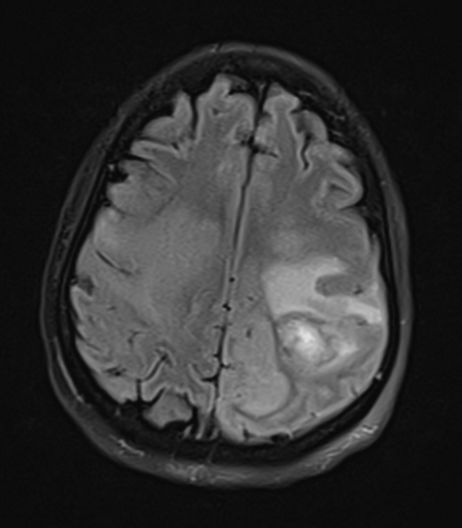

引起血管源性脑水肿的典型疾病包括脑肿瘤、脑脓肿、脑炎等,一些成熟的脑挫伤和脑出血病灶周围也可以出现血管源性脑水肿。相比之下,血管源性脑水肿在白质分布较灰质更为明显,灰白质界限仍然保持,这与离子性脑水肿的灰白质界限模糊有所不同;病变常呈手指状延伸分布模式。CT上可看到脑白质的密度减低,MRI上T1WI呈低信号,T2WI呈高信号,DWI上并不显示明显的弥散受限。

图3 40岁女性,脑脓肿,T2FLAIR像上可见病灶周围片状高信号区域,并呈手指状向周围延伸。